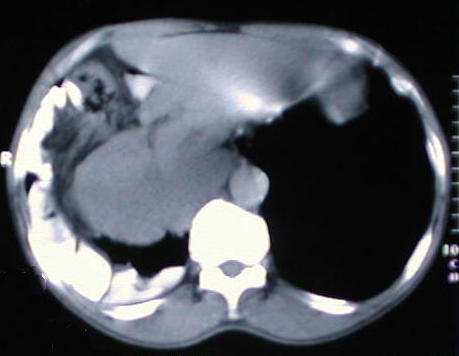

Tomografía de ½ inferior del tórax y abdomen superior con contraste oral, se aprecia desplazamiento del colon hacia la base pulmonar derecha, el campo pulmonar en su periferia y en región subfrénica que comprime y deforma el contorno anterior hepático, también hay contenido de asas delgadas en el tórax.

Corte tomografico del Torax a nivel de la carina bronquial

Corte tomografico del Torax a nivel de la base del torax